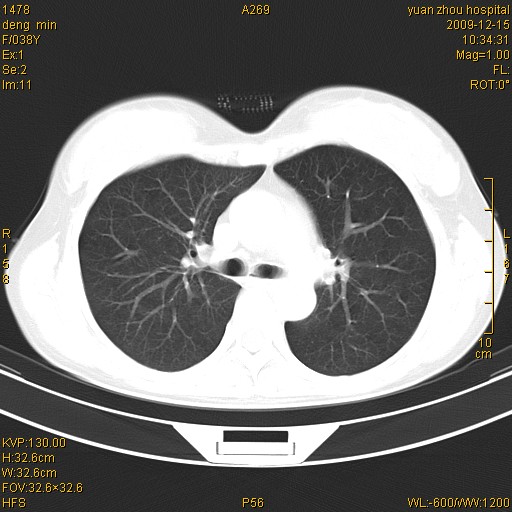

标题: CT23919:F38Y 咳嗽月余 [打印本页]

标题: CT23919:F38Y 咳嗽月余

右肺中下叶、左肺上叶舌段及左肺下叶支气管扩张合并感染。